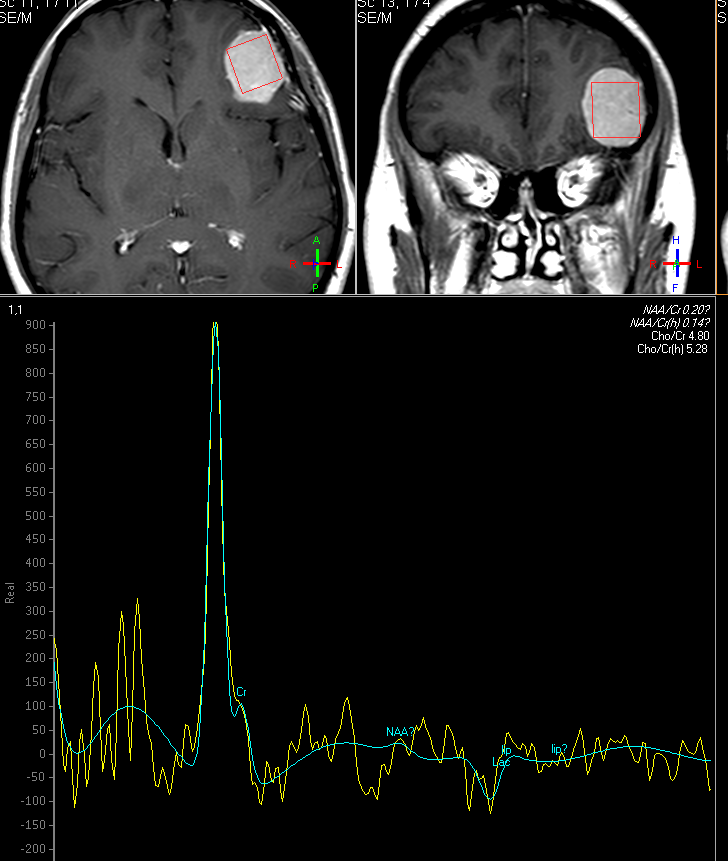

Hoje, a técnica de espectroscopia de múltiplos voxels (MVS) é utilizada com maior frequência, geralmente com tempo de colheita de echo em 144 ms, mas podendo ser utilizado tempos de echo mais longos (288ms), para “limpar” o traçado e quando se deseja obter somente informações dos metabólitos NAA, creatina e cholina.

A técnica de MV tem maior área de abrangência, se aplica melhor para lesões heterogêneas e tem maior resolução para pequenas lesões, devido à possibilidade de usar mini voxels (voxels de pequeno porte). A técnica de múltiplos voxels (MV) evidencia áreas de maior ou menor diferenciação em tumores cerebrais heterogêneos, o que permite direcionar procedimentos por biopsia e é de suma importância na avaliação de invasividade de tecidos cerebrais vizinhos a lesões tumorais.

A técnica de MVS é fundamental na distinção de tumores primários de alto e de baixo grau e na distinção de tumores primários do SNC e implantes metastáticos, cuja distinção nem sempre é fácil por métodos de RM convencionais.

Fig3a,b – Espectroscopia de Múltiplos Voxels (EMV) em caso de glioma de alto grau (Astrocitoma anaplásico – III) frontal esquerdo. Traçados de mini voxels colocados no interior e no tecido cerebral vizinho (a, b), para avaliar grau de invasividade tumoral mostram níveis elevados de cholina dentro e fora da lesão.

Fig3c,d – Espectroscopia de Múltiplos Voxels (EMV) em caso de glioma de alto grau (Astrocitoma anaplásico – III) frontal para sagital esquerdo. Traçados de mini voxels colocados no interior e no tecido cerebral vizinho para avaliar grau de invasividade tumoral mostram níveis elevados de cholina dentro e fora da lesão redução do NAA (c) e acúmulo de lactato(d).

A figura acima apresenta mapa de metabólitos (cholina e NAA) que mostram redução de NAA por substituição de tecido normal por células neoplásicas e acúmulo de cholina por proliferação celular glial (c). Também o mapa de metabólitos (cholina e lactato), mostra, além de acúmulo de cholina, a presença de lactato, inferindo hipóxia intratumoral (d).